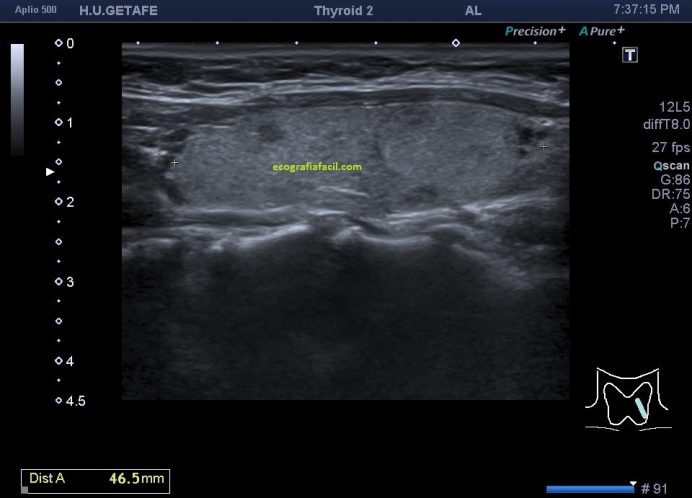

En la imagen 3 y 4 te muestro el desarrollo del estudio normal en esta mujer de 63 años que no tenía ni idea de la ausencia congénita del lado derecho de su tiroides, representado en el corte longitudinal con la imagen 5 donde encontramos «nada» donde debería estar una ecoarquitectura similar a la imagen 4.